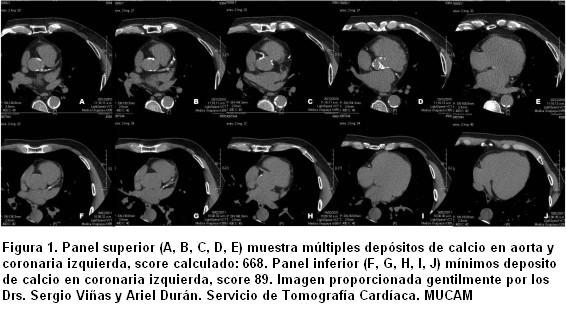

Ya que la calcificación arterial casi siempre representa aterosclerosis, la detección de calcio por TC es un método sensible pero no específico para el diagnóstico de EC obstructiva (8). La presencia de calcio en la pared arterial se define como una densidad mayor de 130 unidades Hounsefield. La extensión de la calcificación de las arterias coronarias es cuantificada usando el score de Agatson (calcium coronary score [CCS]) o el score del volumen de calcio (CVS). El score de Agatson está basado en el coeficiente de atenuación expresado en HU y en la extensión del área de los depósitos de calcio (figura 1) (9).